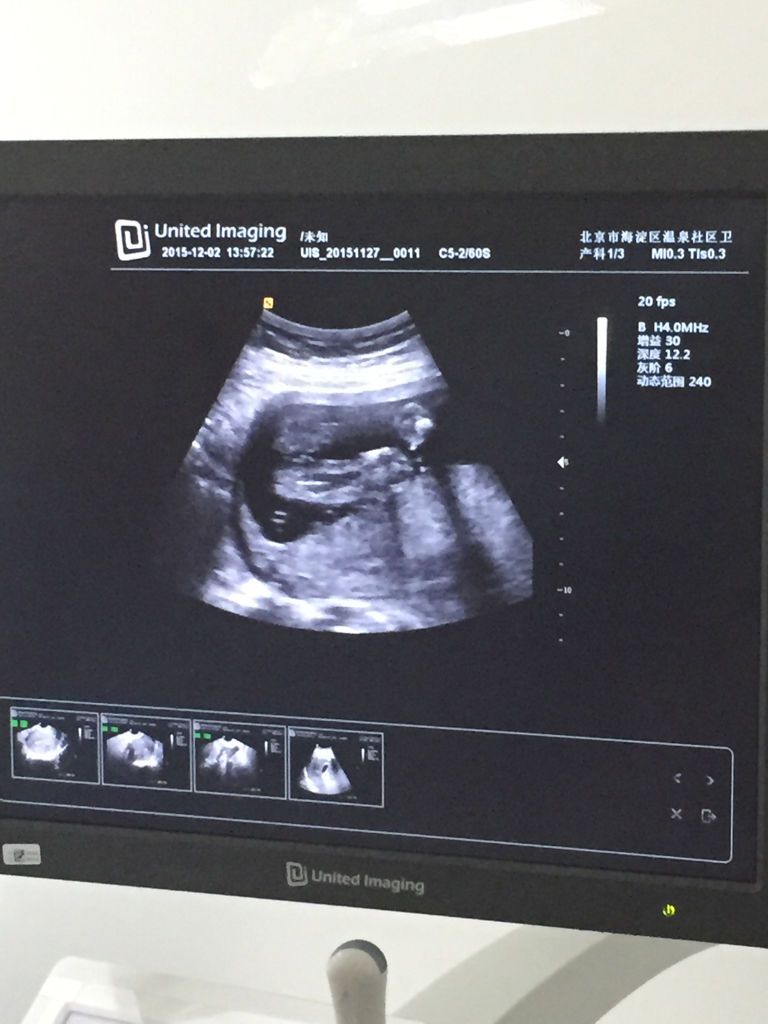

谁能帮看看这两条小腿中间的是男宝宝还是女宝宝,靠左边是屁股 点击展开 匿名用户 2015-12-06 20:01 为您推荐: 其他回答 你这么远怎么看得清楚。 匿名用户 2015-12-06 20:01 相关问题 打小孩的屁股,他小腿左边比右边粗怎么办,孩子一岁半 早上左小腿突然抽筋,今天白天左边屁股偶尔会痛;有什么办法吗? 我老婆哺乳期三个月,现在左边屁股痛、小腿痛